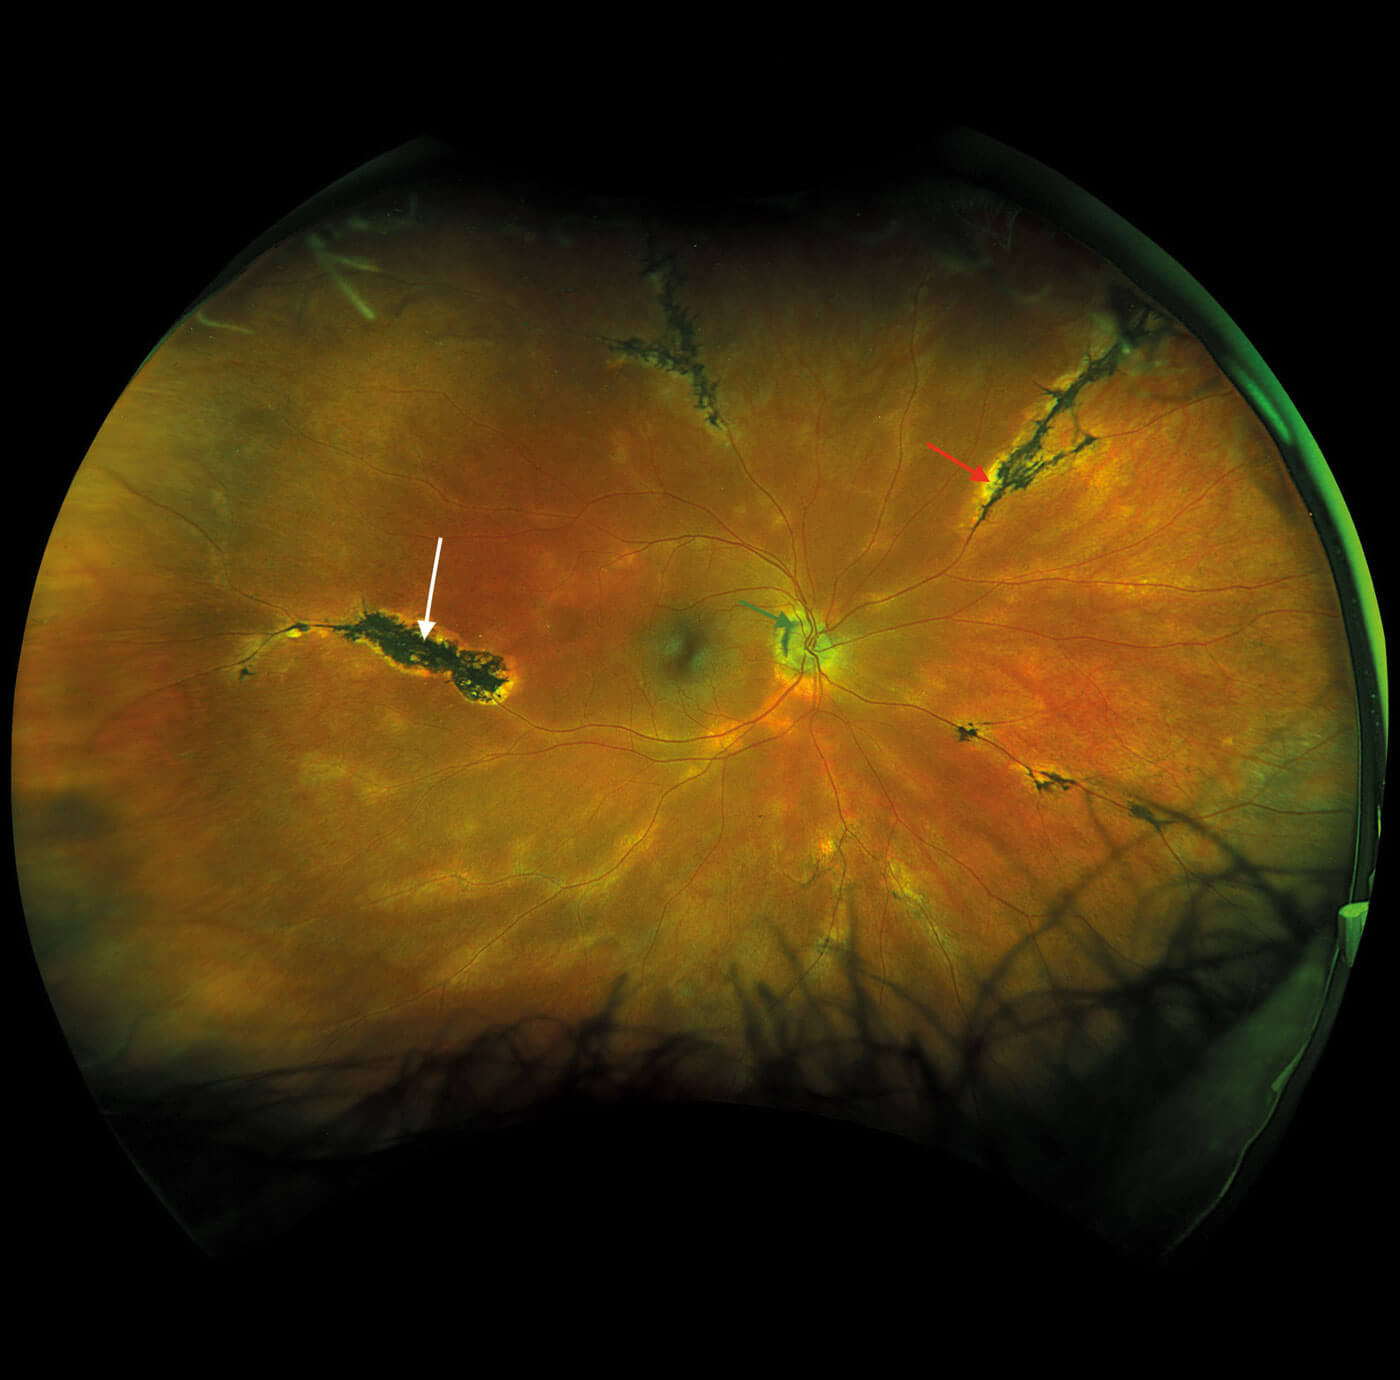

Fundus examination was quite striking in both eyes with bilateral, symmetrical findings. There was evidence of pigment accumulation along the retinal veins, chorioretinal atrophy distributed along the retinal vasculature and elevated, blurred disc margins with a ‘lumpy’ appearance in both eyes.

Figures 1a and 1b: Widefield fundus imaging demonstrating pigment accumulation along the retinal veins (white arrows), chorioretinal atrophy (red arrows) and disc drusen (green arrows).

Widefield fundus imaging demonstrated these clinical findings (Figures 1a, 1b). Fundus autofluorescence showed hypo- autofluorescence in the areas of pigment accumulation and hyperautofluorescence in the areas of chorioretinal atrophy (Figures 2a, 2b). Fundus autofluorescence also showed hyper-autofluorescence at the optic disc indicative of optic nerve drusen. A 30-2 Humphrey visual field test revealed some defects superiorly paracentrally in the right eye. In the left eye there was a more significant field defect with an inferior and superior arcuate defect noted.